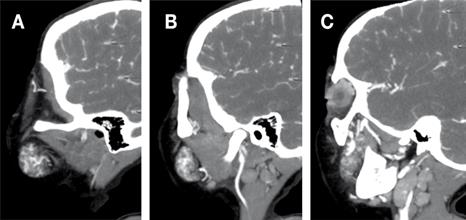

En la tomografía computarizada con contraste se evidenció en la región geniana izquierda, además de las regiones maseterina y pterigomaxilar, una lesión de densidad heterogénea, de predominio hipodenso, sugiriendo componente adiposo, de bordes definidos y delimitados por la fascia de los tejidos blandos vecinos, mide aproximadamente en su porción externa 32 x 17 x 29 mm (región geniano-maseterino) y su porción interna 18 x 13 x 28 mm (región pterigomaxilar), con un elemento vascular central importante, procedente principalmente de la arteria maxilar interna (Figura 3, 4 y 5).

Figura Nº5 . Vista sagital de TAC que muestra masa heterogénea localizada por debajo de la órbita (A), anterior al músculo masetero (B) y con importante vascularización por la arteria maxilar interna (C).